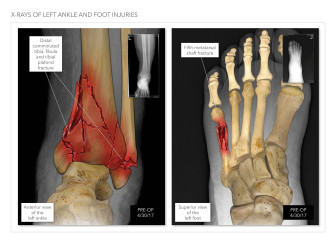

Summary of Left Leg Injuries